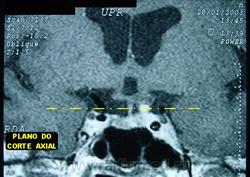

ГМ. Кавернома 2. Кавернома зрительного тракта. +

Кавернома зрительного тракта

Отдел патологии, школа медицинских наук. Государственного Университета Кампинас (UNICAMP). Кампинас, Сан-Паулу, Бразилия.